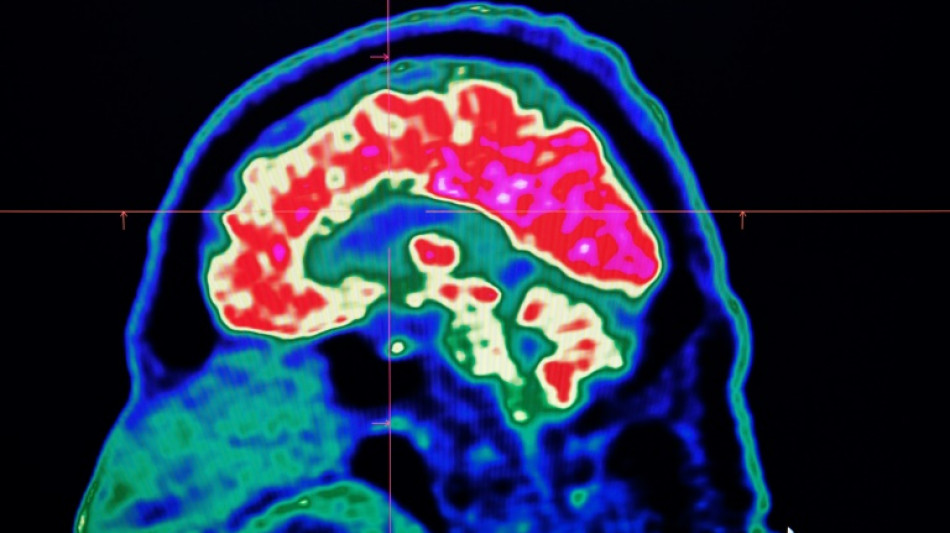

La inteligencia artificial reduce el riesgo de secuelas por un derrame cerebral

El recurso a la inteligencia artificial triplicó el número de pacientes en Reino Unido que prácticamente no sufrieron secuelas tras un accidente cerebrovascular (ACV), anunció el martes el ministerio británico de Salud.

El sistema Brainomix e-Stroke, desarrollado por una empresa con sede en Oxford, permite disminuir en más de una hora el diagnóstico y escoger más rápidamente el tratamiento más adecuado.

Su uso en 110.000 probables casos de ACV sirvió para aumentar el porcentaje de pacientes que no sufrieron ninguna secuela o un porcentaje menor, de entre el 16% y el 48%.

La inteligencia artificial ayuda en la toma de decisiones a la hora de interpretar los escáneres del cerebro y así permitir que los pacientes "reciban el tratamiento adecuado, en el buen lugar y en el buen momento", destaca el ministerio.